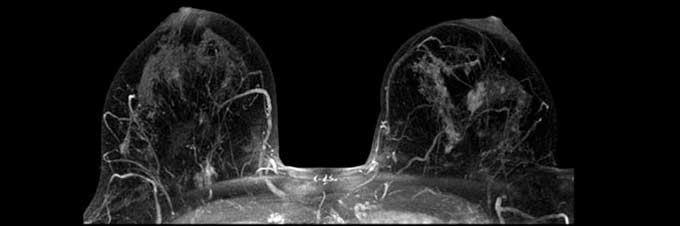

- Магнитно-резонансная томография – предполагает применение контрастного компонента. Осуществляется для выявления рецидива и для оценивания положения материалов железы при установлении имплантата.

| МРТ с контрастированием | Используется в тех случаях, когда необходимо обнаружить рецидивы. |